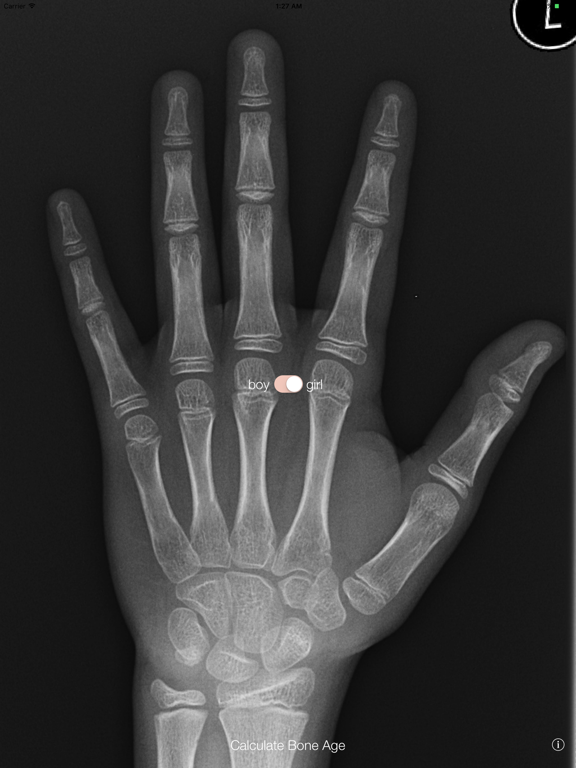

Bone Age

Calculate a bone age without using an atlas right there in clinic using the Tanner-Whitehouse method. Both TWII and TWIII references are included, to give 'RUS', 'TW20' and even carpal scores.